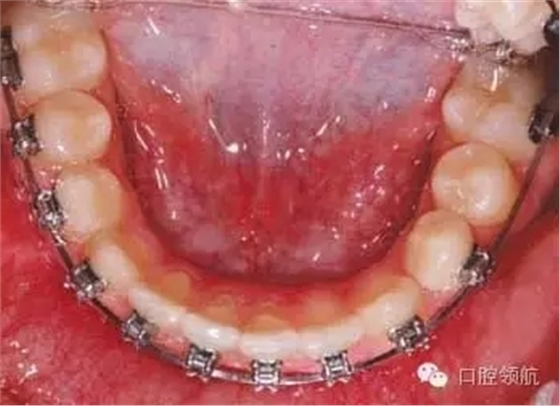

拔除第二恒磨牙后可采用哪種矯治器促進下頜第二前磨牙萌出?

可能的選擇包括使用舌弓防止第一磨牙近中移動,或使用唇擋促進第一磨牙遠中移動并豎直。另外,可以在簡單的下頜固定矯治器上加推簧為第二前磨牙萌出開辟間隙。這種方法可能導致下切牙唇傾前移。這種情況下拔牙6個月后不要采取主動治療措施。豎直并遠中移動第一磨牙期間前磨牙會自動萌出。